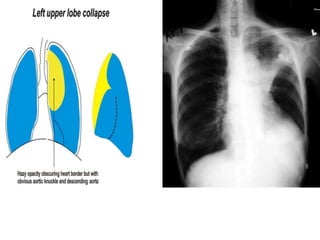

LOBAR ATELECTASIS

Radiologic signs of lobar atelectasis :- Direct

or Indirect .

Direct signs include increased opacification

of the airless lobe and displacement of

fissures.

Indirect signs include displacement of hilar and

cardiomediastinal structures toward the side of

collapse, narrowing of the ipsilateral intercostal

spaces, elevation of the ipsilateral

hemidiaphragm, compensatory hyperinflation

and hyperlucency of the remaining aerated

lung, and obscuration or desilhouetting of the

structures adjacent to the collapsed lung

(eg, diaphragm and heart borders). Additional

radiologic features vary according to the site of

atelectasis.